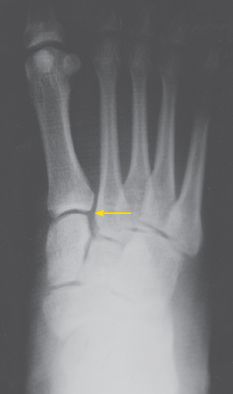

Lisfranc Ligamental Injury

After a fall during a soccer match 2 weeks earlier, a 26-year-old woman had pain of the right midfoot, with moderate swelling. The pain was aggravated with a normal gait and alleviated with an antalgic gait, specifically with inversion of the right ankle such that most of the weight from heel-strike through toe-off transmitted forces from the lateral calcaneus through the fifth metatarsus to the fifth phalanx.

Point tenderness was noted over the right midfoot. No plantar ecchymosis was evident. Results of squeeze, Thompson, anterior drawer, and talar tilt tests were negative. Further squeeze testing of the metatarsal rays elicited pain in the midfoot.

Anteroposterior radiographs of the right foot demonstrated a gap larger than 3 mm between the bases of the first and second metatarsals as well as between the first and second medial cuneiforms, with loss of alignment of the medial edge of the base of the second metatarsal with the medial edge of the medial cuneiform. This was a stage II sprain according to the Nunley and Vertullo classification.1 There was no fracture of the base of the second metatarsal.

Capsuloligamentous disruption of the Lisfranc joint is most often seen in patients who have sustained high-velocity trauma in motor vehicle crashes. However, it can also result from low-velocity twisting-type injuries that occur in athletes.2

A clinical diagnosis can be made on the basis of midfoot swelling and tenderness; plantar ecchymosis; and assessment of gait, medial longitudinal arch, and ability to bear weight on the toes. Pain on squeezing the metatarsal rays in frontal and coronal planes is diagnostic.

The evaluation of a suspected Lisfranc joint injury should include weight-bearing anteroposterior, oblique, and lateral radiographs of the foot.1 About 20% of Lisfranc joint injuries are missed on conventional radiographs, presumably because of lack of fracture or history to correlate with the findings.3